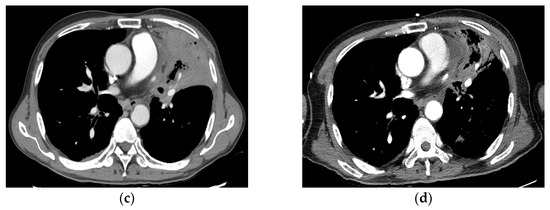

3.4. Partial Response

| 9 | 66, M | 30.3 | Salvage | tuberculosis | current (55 PY) | rcT0N2M1 | LUL Lt prevascular | SqCC | Chemotherapy | 7.1 | 60 Gy/10 fx | PR |

| 13 | 65, M | 12.6 | Primary | no | ex-smoker (40 PY) | cT2N1M0 | LUL Lt Interlobal LN | SqCC | Lt pneumonectomy | 47.2 | 60 Gy/10 fx | PR |

| 19 | 68, M | 6.3 | Primary | Pneumoconiosis, COPD, old Tb (40 years ago) | ex-smoker (30 PY) | cT2N0M0 | LUL | SqCC | Lt pneumonectomy | 29.0 | 55 Gy/10 fx | PR |